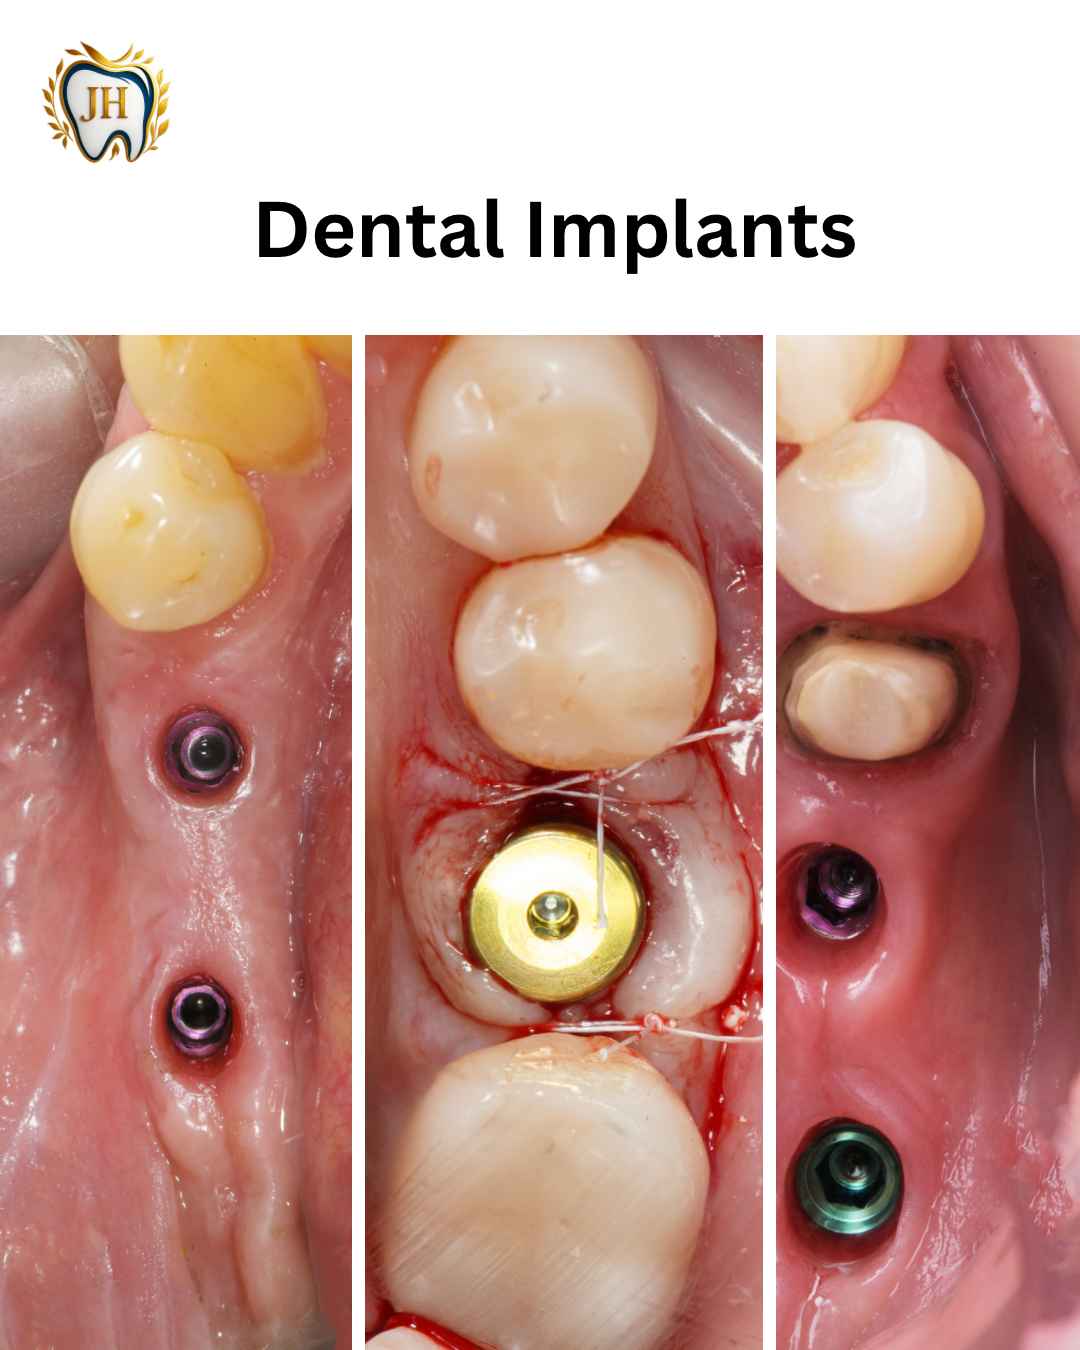

- Dental Implants